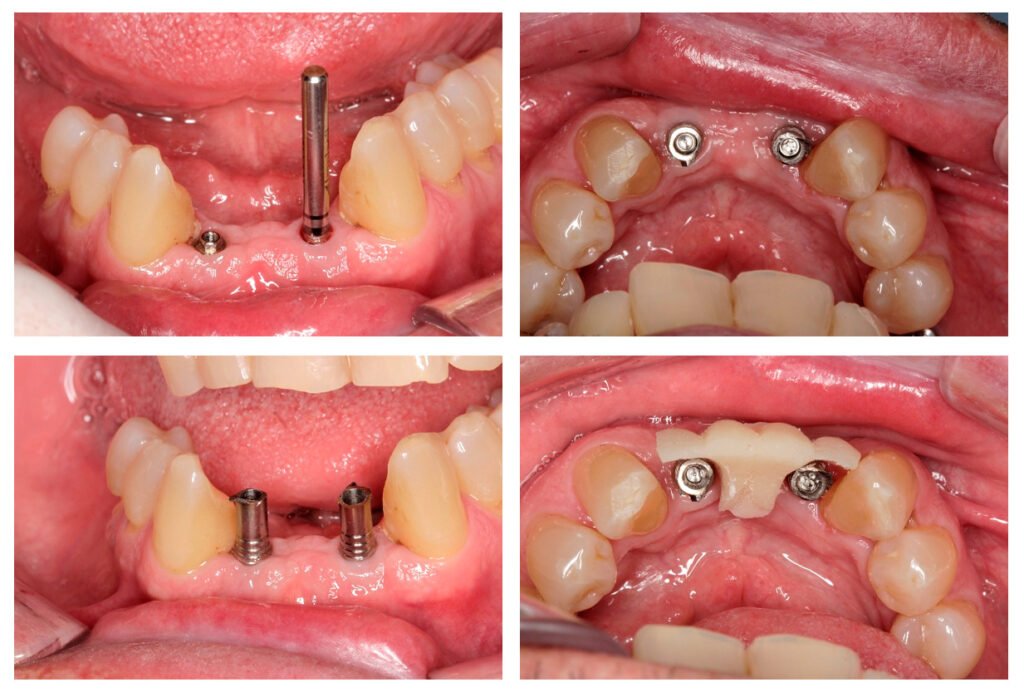

Avaliamos o espaço mésio-distal entre os dentes 33 e 43 e constatamos a ausência de distância para a colocação de implantes individualizados. Assim sendo, optamos pela instalação de dois implantes Veloce CM de diâmetro 3.3 e pilares do tipo micro-cônico para a solução clínica.

Dessa forma, na matéria desta semana, será abordada uma situação clínica de espaço mésio-distal restrito com o uso de implantes híbridos do tipo Veloce CM estreitos de 3.3 de diâmetro e posterior confecção de prótese sobre implantes com pilares intermediários do tipo micro-cônico.